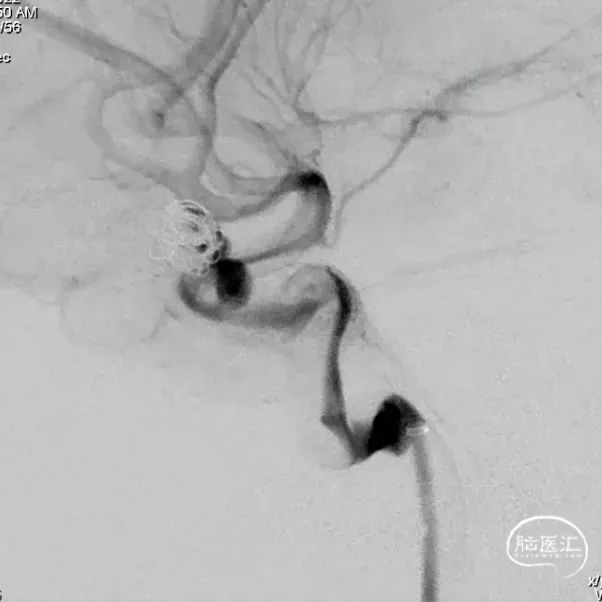

术后6个月造影随访提示动脉瘤完全愈合,载瘤动脉通畅。

4、该病例即刻造影显示血流重构满意,瘤腔内血流明显淤滞。术后六个月及12个月随访,均显示动脉瘤愈合,载瘤动脉通畅无狭窄。